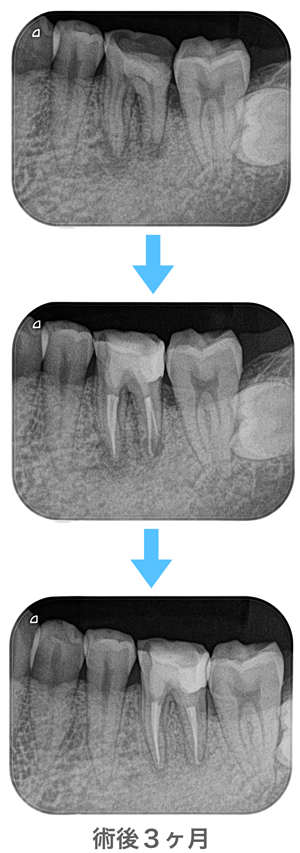

経過観察

(※上記の画像とは別の歯になります)

根尖に病変があっても、無菌的環境下(ラバーダム防湿)で科学的根拠(エビデンス)に基づいた治療を行うことで、術後3ヶ月には根尖病変は消失し、そこは健全な骨に置き換わりました。